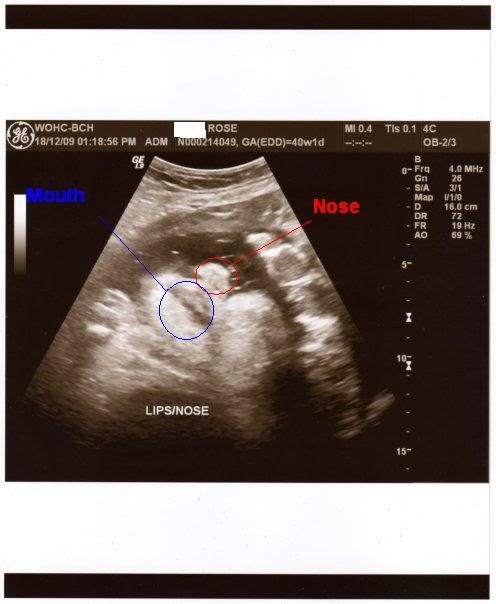

EDIT: Apparently you mofos didn't pray hard enough LOL Anyways, here's the pic we got today. It's his lips and nose.

http://i167.photobucket.com/albums/u...527/img003.png

Also; i can't tell where his lips/nose are. I hate ultrasounds since i can never really understand what is where @.@ once in elementary school my teacher brought a ultrasound to the classroom and i couldnt seen him so i pointed at a random part and said IS THIS IT?!...aparrently not if ya know whut i mean. god i was so embarrassed.

What a nice christmas present, congratulations. At at the second ultra sound picture in the top left corner, is that the G-E money symbol? Do they advertise in Ultrasounds now? LOL Devon's a unique name, never heard of it.